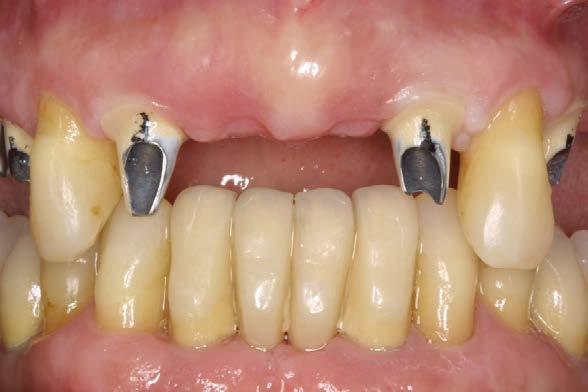

Figuras 2-3. Imágenes intraorales que evidencian pérdida ósea generalizada, extrusión de dientes anteriores y recesiones en todas las piezas presentes.

ósea vertical generalizada, defectos angulares en sectores posteriores y múltiples ausencias dentarias en ambos maxilares. La inspección intraoral mostró recesiones gingivales, exposición radicular y colapso del tercio anterior como consecuencia de migración dentaria y pérdida de soporte (Figura 1-3).

En la zona anterior maxilar se realizaron pruebas estéticas detalladas, optimizando aspectos como líneas medias, troneras y pónticos (Figura 6-8). En el arco inferior, se conservaron los

caninos y premolares mediante tratamiento periodontal intensivo. Esta decisión favoreció la integración funcional de dientes e implantes, manteniendo la propiocepción y mejorando el control de posibles sobrecargas funcionales como el bruxismo.22-24

La paciente continúa en seguimiento. A los 8 años, la estabilidad de los tejidos duros y blandos, así como la estética de la rehabilitación, era completa (Figura 9-11). A los 12 años se observó

una buena progresión del tratamiento, sin cambios reseñables (Figura 1214). A los 20 años de seguimiento se constató una evolución estable, sin pérdida ósea en dientes ni implantes, y con buena salud de los tejidos periimplantarios (Figura 15-17).

Conservar piezas naturales en tratamientos combinados tiene implicaciones

no solo clínicas, sino también sensoriales y psicológicas.16,17,31,32 La propiocepción que brindan los dientes remanentes mejora la distribución de fuerzas y facilita el control funcional. Esta ventaja se potencia cuando los dientes preservados forman parte de guías funcionales clave, como los caninos.33,34

Además, los dientes unirradiculares suelen presentar una mejor respuesta al tratamiento periodontal en casos de EP avanzada, ya que su anatomía es más accesible para el control mecánico y presentan menor afectación en furcaciones.35,36 Como se evidenció en este caso, el compromiso del paciente, junto con un seguimiento clínico riguroso y personalizado, fue determinante para lograr estabilidad a largo plazo. 37